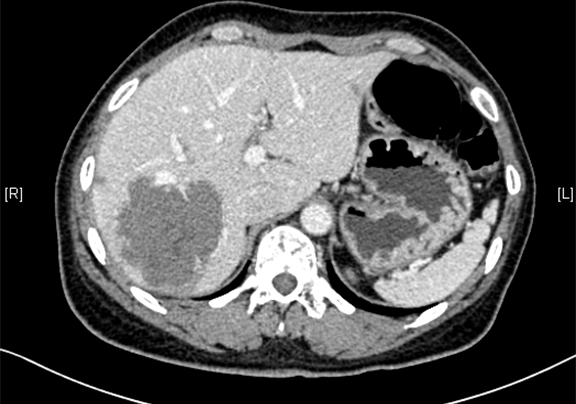

现病史:患者于10天前因右上腹外伤于当地医院查体发现肝占位,右上腹隐痛,无腰背部放射痛、皮肤巩膜黄染、恶心、呕吐、寒战、高热、腹泻、血便、咳嗽、咳痰、胸闷、气短、尿频、尿急、尿痛、血尿。行上腹部增强CT示:肝脏多发血管瘤可能性大,胰尾部小囊肿可能性大,左侧输尿管扩张积水,建议手术治疗。

辅助检查: 下腹部增强CT示:考虑肝脏多发血管瘤可能性大。

术前CT检查:动脉期

静脉期

平衡期